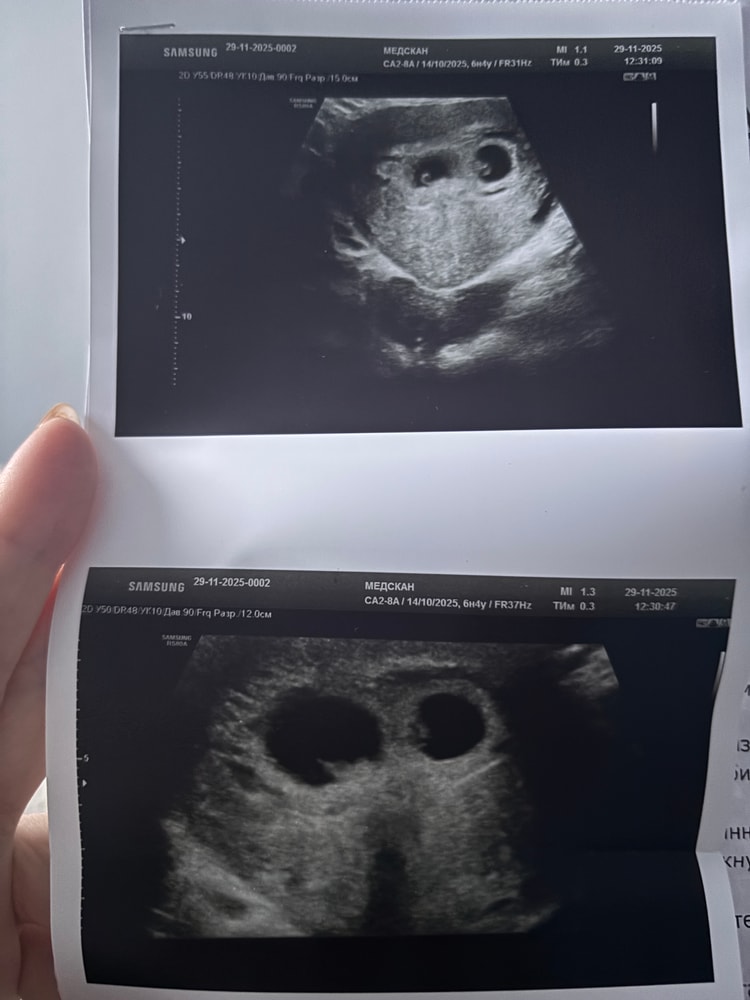

Подскажите пожалуста как у вас рос хгч? У меня на 9дпо был 19,5, на 12-79, 5, а на 17дпо 807. Была двойная овуляция